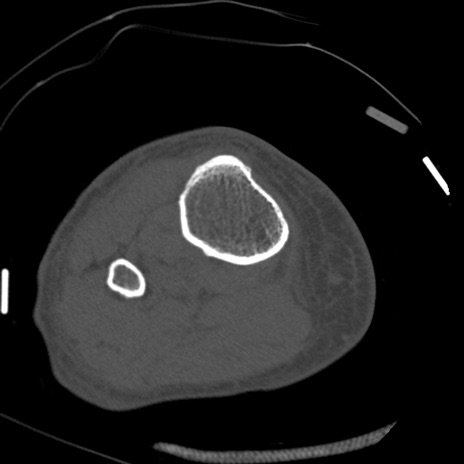

症例28 右膝関節CT(横断像)

右膝関節CT